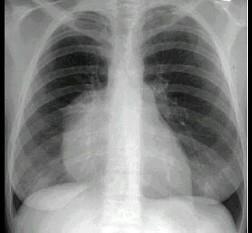

问题 女,18岁,自感胸闷,X线检查见纵隔占位,CT检查如图,最可能的诊断为 ( )

选项 A、淋巴瘤 B、下纵隔胸腺瘤 C、上纵隔胸腺瘤 D、胸内甲状腺瘤 E、纵隔畸胎瘤

答案 E